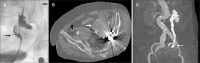

Arterioureteral fistula is a rare but life-threatening condition. An endovascular treatment approach is commonly used; however, there is a potential risk of infection. We present a case in which a patient presented with abdominal pain and was diagnosed with a ruptured internal iliac artery aneurysm and a subsequent arterioureteral fistula. An aortic stent graft was inserted to treat the arterioureteral fistula, but it subsequently became infected, resulting in the patient's death. This case underscores the importance of early diagnosis and treatment of arterioureteral fistula and the possibility of graft infection.